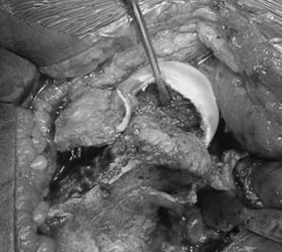

Treating SCFE:  Orthopedists use all of the above information in order to determine the most appropriate treatment for your son or daughter.  There is no role for non-operative treatment in SCFE.  The consequences of simply observing a slip is that it may get worse and go on to develop AVN.  AVN is a horrible complication that we try to avoid at all cost.  For mild slips, we place a special screw into the femur to hold it in place and keep it from getting worse.  This essentially helps the growth plate turn into even stronger "super glue" and eventually harden so that the femoral head cannot move any more.  We often use this same treatment for moderate slips as well.

A newer, and less aggressive approach which has been popularized by Dr. Klaus Parsch calls for opening the hip joint capsule in order to release the pressure that has built up, and then only partially put the femoral head back in place before holding it there with a couple screws or pins.  With this technique, there was only a 10% AVN rate, but we again have to call into question the fact that the patients in this research were European and the low AVN rate may not necessarily be replicated here in North America.